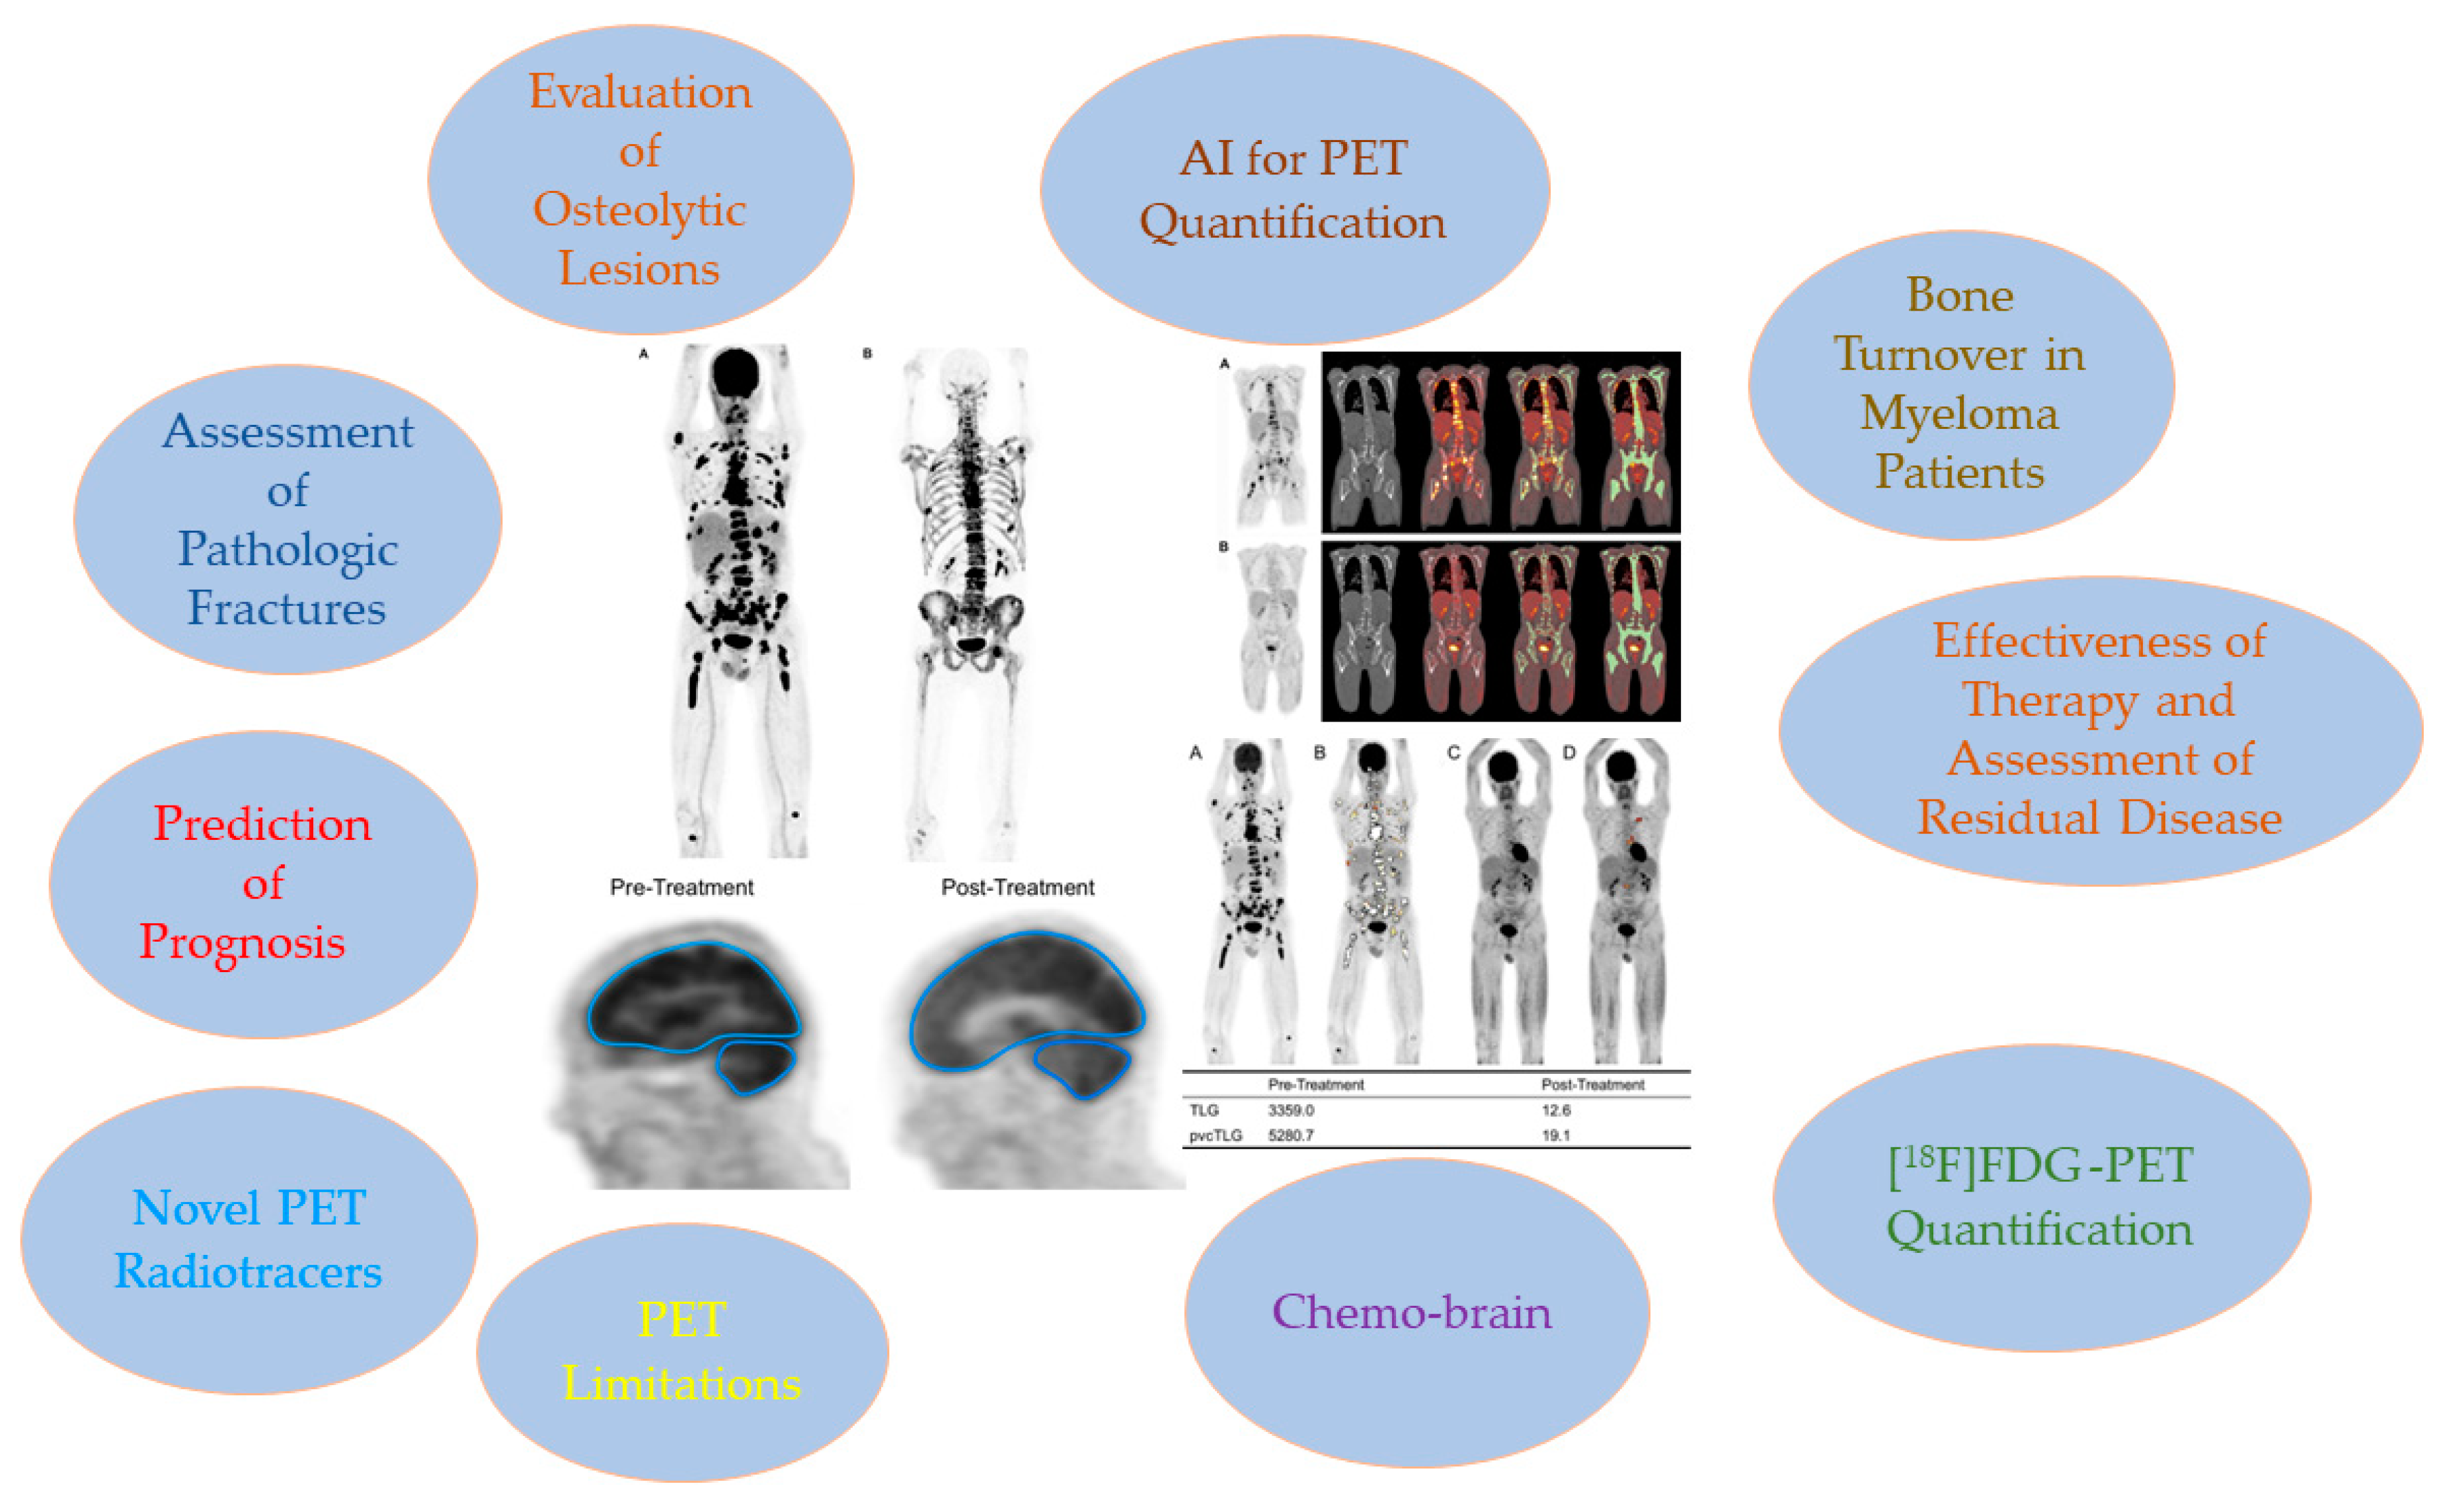

Significance of PET/CT Imaging in Myeloma Assessment: Exploring Novel Applications beyond Osteolytic Lesion Detection and Treatment Response

2. Assessment of Bone Disease in MM: An Examination of Osteolytic Lesions

3. Prediction of Prognosis

4. Importance of [18F]FDG PET/CT in Assessing Treatment Efficacy

4.1. Baseline Parameters of [18F]FDG PET

4.2. Assessment of Myeloma Patients after Treatment

5. Identification of Minimal Residual Disease (MRD) in Myeloma

7. Assessment of Pathologic Fractures

8. PET for Assessment of Bone Turnover in Myeloma Patients

9. Chemo Brain

10. [18F]FDG PET Quantification

12. Novel PET Radiotracers

13. AI for PET Quantification

15. [18F]FDG and PET Limitations